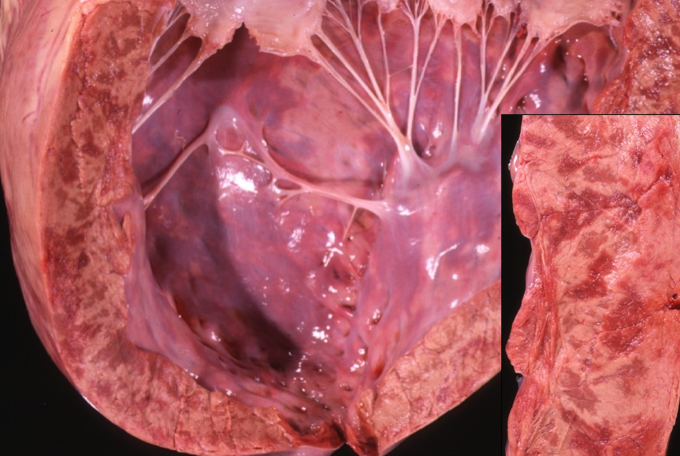

What are the features of mulberry heart disease in pigs?

Peroxidation of the cell membranes due to Vit E/ selinium deficiency

Necrosis

Hydropericardium

Haemorrhages